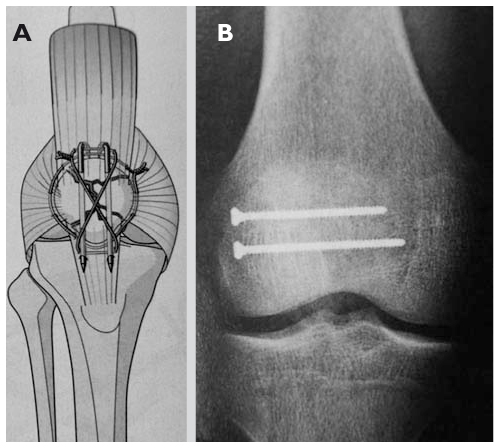

Cerclage Entre La Patella Et Le Tibia Dans Le Cadre D Une Section Du Download Scientific Diagram

Radiographie De Face Apres Reparation Du Tendon Rotulien Et Protection Download Scientific Diagram